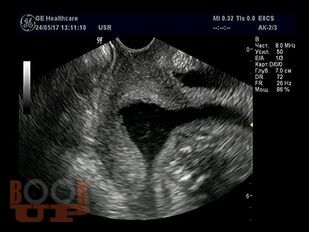

Методические рекомендации посвящены особенностям ведения беременных с истмико-цервикальной недостаточностью и пролабированием плодного пузыря. Представлен обзор зарубежных и отечественных представлений об этиопатогенезе, методах диагностики ИЦН. В методических рекомендациях подробно описана методика хирургической коррекции при пролабировании плодного пузыря, представлен иллюстрационный материал об этапах операции, а также имеется информация об особенностях предоперационной подготовки и введения в послеоперационном периоде. Представлены данные о возможности прогнозирования развития ИЦН на амбулаторном этапе вне беременности. Рекомендации содержат рисунки, таблицы, тестовые задания и ситуационные задачи. Методические рекомендации предназначены для врачей акушеров-гинекологов.